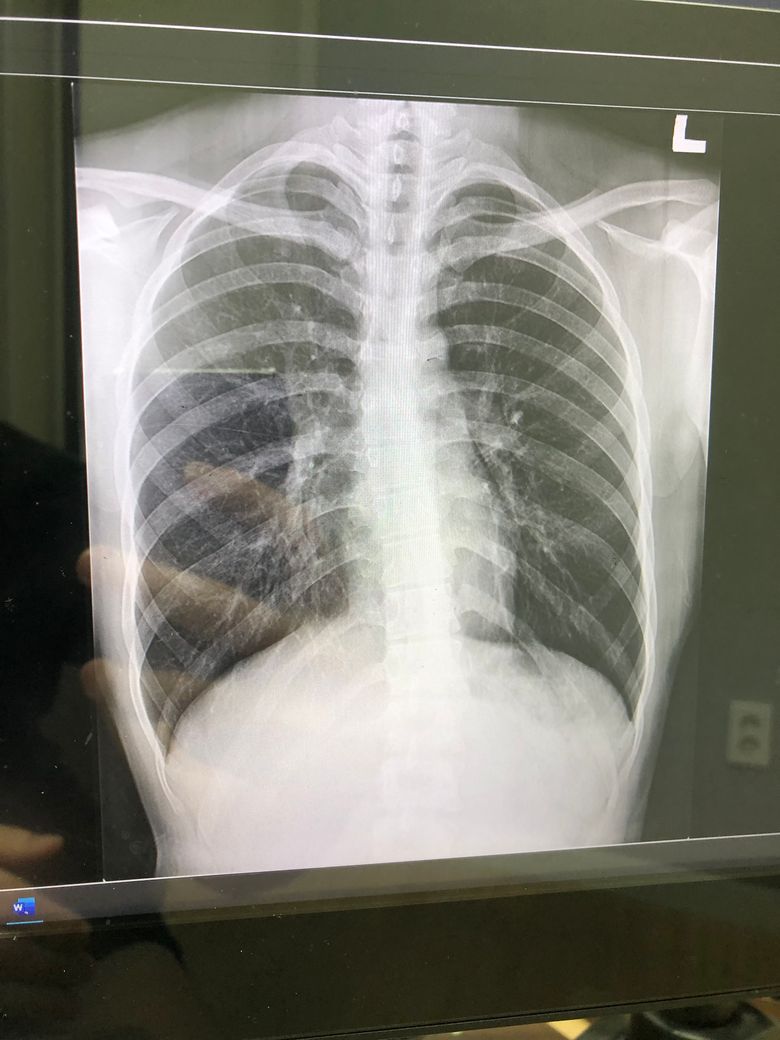

혹시 이 엑스레이 사진보고 폐에 무슨 이상이 있는지 알려주실수 있나요

폐 엑스레이 사진인데 담당의사는 좀 더럽긴한데 ct까지 찍을 필요는 없다고 해서 그냥 왔는데 다른의사분들 의견이 궁금해서요 그리고 폐건강 때문에 연초는 안피고 액상전담을 피고 있는데 액상전자담배도 폐건강에 악영향을 끼치는지 궁금합니다ㅠ

해상도 문제로 자세한 확인은 어렵습니다만 이상소견이 뚜렷하진 않습니다.

액상 전자담배 역시 담배이며 액상의 경우 연초보다 양을 가늠하지 못해 더 많은 양의 흡연을 하는 것으로 조사된 연구 결과도 있습니다.

건강을 위해 금연을 권합니다.